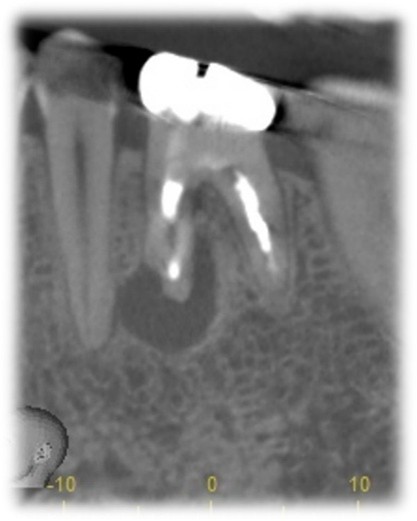

即時埋入で対応できることを確認

根の先には根尖病変(虫歯が原因で骨が溶けてしまっている状態)もありましたが、即時埋入で対応することができると判断しました。

条件によっては即時埋入が出来ないことも多くありますが、もし即時埋入が可能であれば術後の痛みや腫れも少なく、短期間で冠をかぶせることが出来ます。

約40分の治療時間で抜歯とインプラント埋め込みが終了しました。